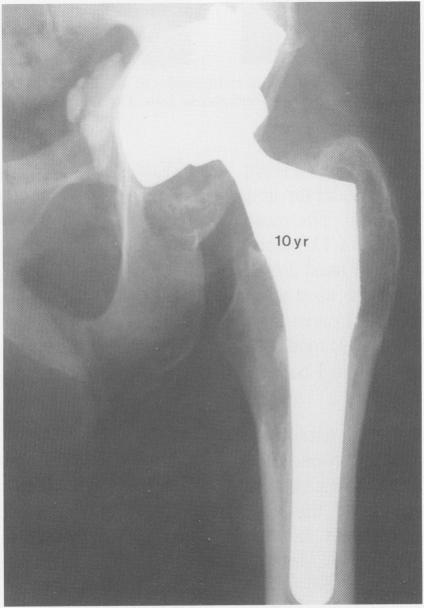

无骨水泥型马洛里-黑德初次全髋关节置换术的结果:5至7年的回顾

Results of the cementless Mallory-Head primary total hip arthroplasty: a 5 to 7 year review.

We reviewed the results of 172 plasma-sprayed, titanium primary total hip arthroplasties inserted without cement and followed 5 to 7 years. Hips were replaced for a wide range of diagnoses and patient ages. No femoral components had been revised nor were any considered unstable. Clinical results have been excellent; 88% of hips had either no or slight amount of pain and only 5% of patients had thigh pain when specifically asked. Radiographically, this femoral component achieved stability after an initial subsidence in 9% of cases. Extensive femoral bone resorption was rare, and distal cortical hypertrophy was commonly seen. Pelvic osteolysis occurred in 16 (9%) cases and was considered major in 10 of these. It was the cause of failure of 3 acetabular components. Femoral endosteal lysis was not observed. We concluded that mechanical stability of the Mallory-Head titanium total hip prostheses is excellent. However, significant pelvic osteolysis had occurred commonly with this implant design, and will continue to pose major reconstructive problems in the future.

摘要